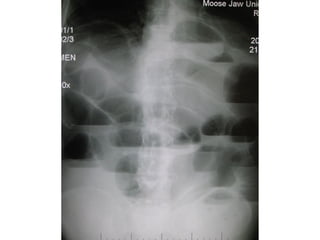

Investigations:

• Radiographs are essential to confirm the diagnosis

and accurate the site of the obstruction.

• The radiological diagnosis is based on a

supine(erect) abdominal radiograph.

• If conditions of the patient are poor a lateral

decubitus position view may be taken.

• Usually can determine whether small bowel, colon

or both are distended.

• Radiographs show multiple gas-fluids levels, with

distended bowell resembling an inverted U.

• Obstruction of the small bowel outlines the valvulae

conniventes, which occupy the entire transverse

diameter of the bowel image.

• Small bowel pattern occupies the more central portions

of the abdomen.

• Large bowel obstruction shows haustral markings, that

occupies only a portion of the transverse diameter of

the bowel, unlike valvulae conniventes, are spaced

irregularly and the indentations are not placed

opposite one another.

• Large bowel pattern occupies the periphery or pelvis

portion of the abdomen.

• A distended caecum is shown by a rounded gas shadow

in the right iliac fossa.

Investigations: • Radiographs areessential to confirm the diagnosis and accurate the site of the obstruction. • The radiological diagnosis is based on a supine(erect) abdominal radiograph. • If conditions of the patient are poor a lateral decubitus position view may be taken. • Usually can determine whether small bowel, colon or both are distended. • Radiographs show multiple gas-fluids levels, with distended bowell resembling an inverted U.

• 19.

• Obstruction ofthe small bowel outlines the valvulae conniventes, which occupy the entire transverse diameter of the bowel image. • Small bowel pattern occupies the more central portions of the abdomen. • Large bowel obstruction shows haustral markings, that occupies only a portion of the transverse diameter of the bowel, unlike valvulae conniventes, are spaced irregularly and the indentations are not placed opposite one another. • Large bowel pattern occupies the periphery or pelvis portion of the abdomen. • A distended caecum is shown by a rounded gas shadow in the right iliac fossa.